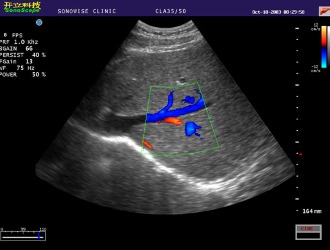

В процессе диагностики могут быть использованы следующие методы:

- УЗИ сосудов или ультразвуковая допплерография – для анализа кровотока в артериях вертебро-базилярной системы (измеряется скорость кровотока и проверяется наличие окклюзий);